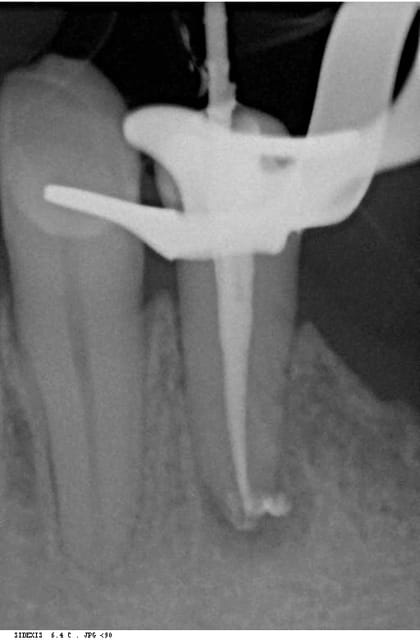

mon faux canal en faisant un rtt

> > voilà une radio avec une autre incidence: tu

> vois

> > le canal palatin? tu vois l'obturation dedans?

> t'as rattrapé la courbure, pour le palatin,c'est

> flou, il me semble que cette racine a une

> structure osseuse,mais bon,je vais changer de

> lunettes!mais on n'est pas mardi matin